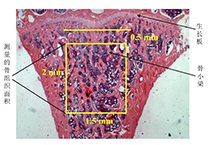

| AG1007 | 結(jié)果描述 | 對(duì)骨形態(tài)計(jì)量的結(jié)果進(jìn)行結(jié)果描述 |